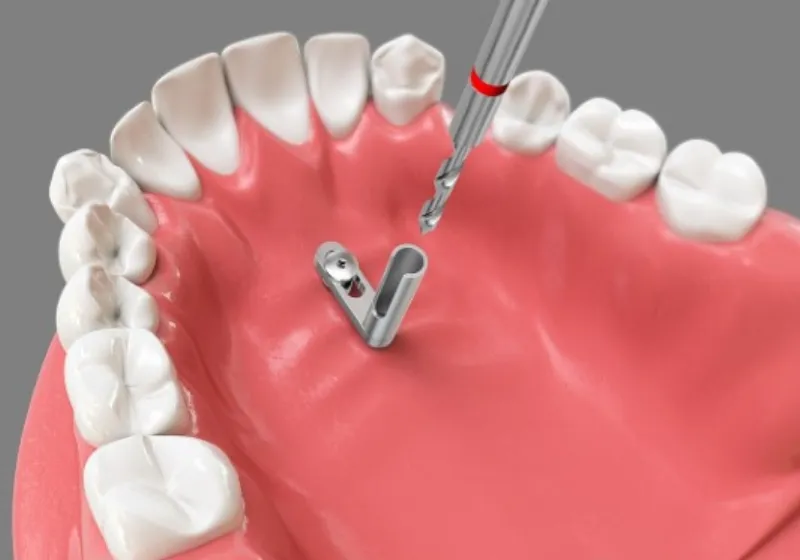

インプラント矯正は、顎骨に小さな矯正用アンカースクリュー(インプラント)を埋め込み、それを歯の移動の固定源として利用する治療法です。この方法により、歯を効率的に移動させることができ、治療期間の短縮が図れます。一般的な矯正方法では動かしづらい奥歯の後方移動に効果的なほか、抜歯が必要な症例を非抜歯で治療できる可能性も高まります。また、3Dメタルプリントで一人ひとりに合わせて作製した矯正補助装置と連結することで、治療の幅がさらに広がります。

矯正用アンカースクリュー

(ミニインプラント)とは

矯正用アンカースクリューは、ミニインプラントともよばれますが、失った歯の代わりとして使用される人工歯根のインプラントとは別のものです。材質は生体との親和性に優れたチタンである点は同じですが、サイズは直径1~2mm、長さは6~10mmほどとかなり小さく、歯肉の切開や顎骨に穴をあけるなどの手術は不要です。また、人工歯根のインプラントとは異なり、矯正治療の終了後はすぐに取り外すことができます。永久的に歯肉に埋め込むわけではないので、ご安心ください。

- Step 05

アンカースクリューを

埋め込む歯肉の上から矯正用アンカースクリューを埋め込みます。局所麻酔してから処置を行なうので強く痛むような心配はありません。 1本につき3分ほどで埋め込むことができます。